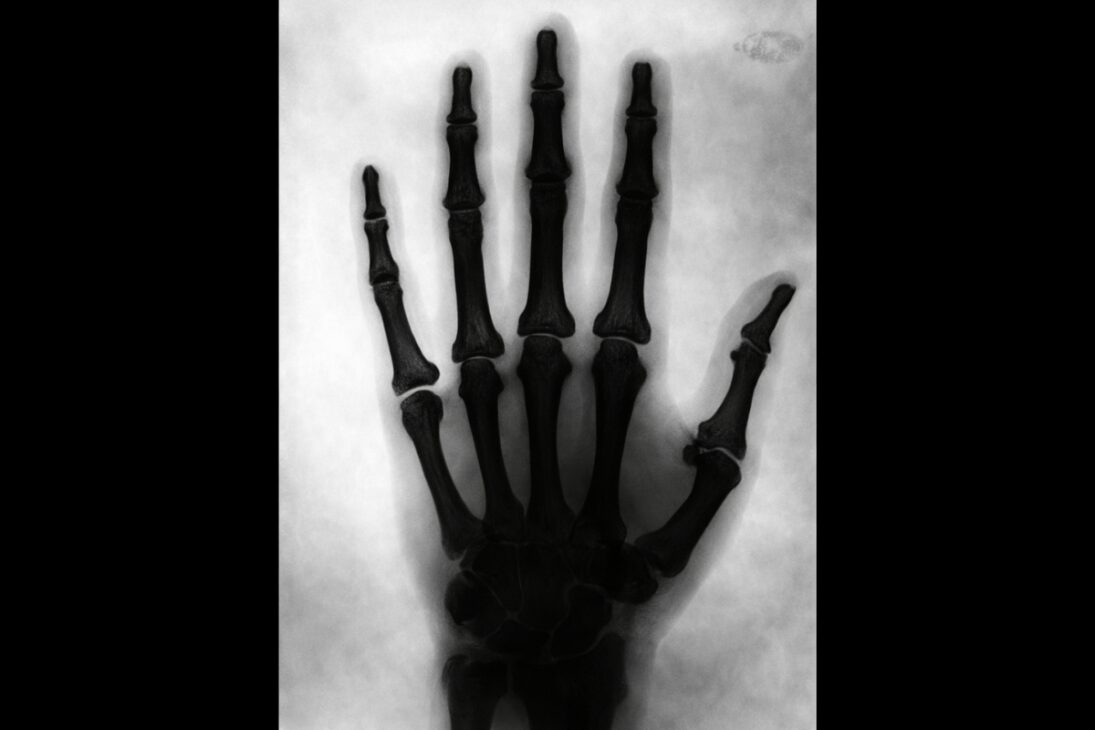

Nikola Tesla hizo algo que aún hoy impresiona cuando se habla de tecnología y ciencia. En 1896, ya estaba produciendo imágenes radiográficas de su propio pie y de su propia mano, pocos meses después del anuncio oficial del descubrimiento de los rayos X por Wilhelm Conrad Röntgen, en noviembre de 1895.

Tesla utilizó bobinas de alta tensión y tubos de descarga a vacío desarrollados por él para generar las imágenes. El resultado fue la producción de radiografías de su propio pie y de su propia mano aún en 1896.

Mientras el término rayo X se popularizaba rápidamente en la prensa internacional entre 1896 y 1897, Tesla prefería llamar a estas imágenes shadowgraphs, reforzando un vocabulario propio para un fenómeno que aún se estaba entendiendo.